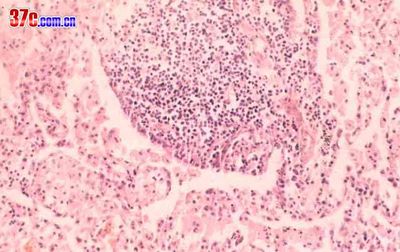

肺炎性假瘤是成纤维细胞.淋巴细胞.浆细胞.异物巨细胞.组织细胞及泡沫细胞等组成的肉芽肿。

肺炎性假瘤(inflammatory pseudotumor)①:胆固醇肺炎,示肺泡间隔内由淋巴细胞增生聚集而成的小团块,像花蕾样突入肺泡道内,略似淋巴滤泡,但无生发中心。he×200。

肺炎性假瘤(inflammatory pseudotumor)②:示肺泡腔内的泡沫细胞。he×400。

肺炎性假瘤(inflammatory pseudotumor)③:示巨噬细胞、泡沫细胞、淋巴细胞及浆细胞。有些巨噬细胞胞浆含有含铁血黄素颗粒。he×400。

肺炎性假瘤(inflammatory pseudotumor)④:肺浆细胞肉芽肿,肉芽组织内主要为成熟性浆细胞,此外,还可见淋巴细胞及泡沫细胞等。he×200。

肺炎性假瘤(inflammatory pseudotumor)⑤:正常组织结构消失,纤维结缔组织广泛增生,肺泡上皮细胞增生形成假腺腔样结构。

肺炎性假瘤(inflammatory pseudotumor)⑥:肺泡及支气管结构消失,而呈炎性肉芽组织构像。he×100。